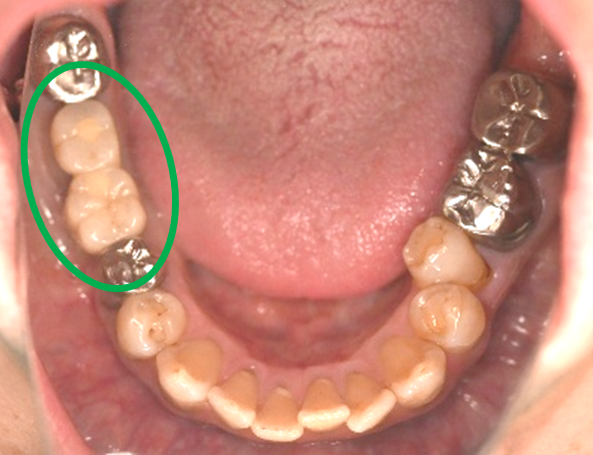

After

※緑丸は、今回埋入したインプラント

※黄色丸は、2006年10月に埋入したインプラント